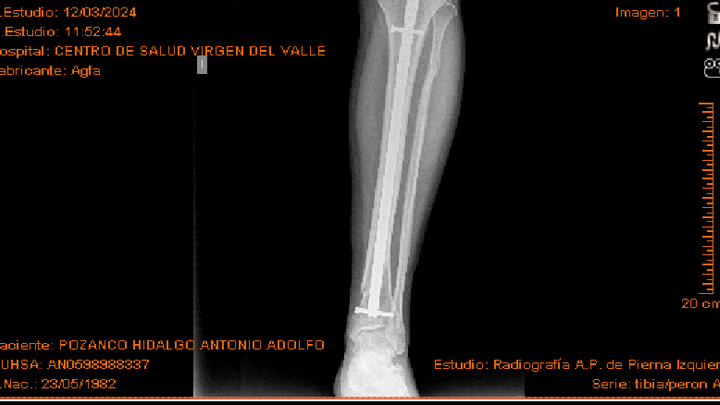

Hola, mi nombre es Antonio tengo el síndrome de asperger y también soy superviviente de maltrato infantil y me fracture la tibia y peroné hace 2 años y casi 4 meses.

Llevo casi un año que no salgo de las 2 calles continuas a mi casa. Sinceramente creo que el clavo me molesta mucho y he encontrado un traumatólogo que me quita el clavo por un precio bastante asequible.

Por recomendación de un amigo también comento que lo he intentado por la seguridad social. En principio fui a una revisión de la pierna en Barcelona donde vivía en esos momentos y me dijeron que al año y medio me lo quitaban, pero cuando pasó el año y medio por circunstancias me tuve que mudar a Andalucía y fui a la revisión de aquí de Ecija y rápidamente me dijeron que no me lo quitaban. Pedí segunda opinión en virgen del Rocío de Sevilla capital y fue muy rápido con respuesta negativa, así que mi única opción es hacerlo por privado.